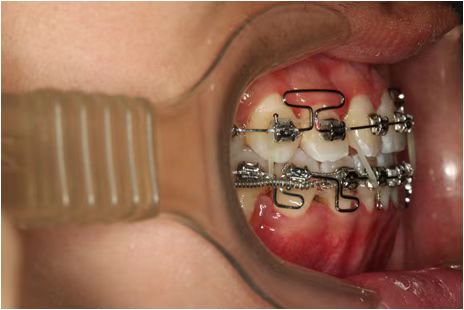

情况:不接受外科手术,在当地做了1年半的矫治,遇到困难无法进行。由外地正畸同行推荐来上海寻求非手术矫治的二手病例。武广增老师接收时的错合畸形情况,呈现严重的骨性反合偏合及侧方开合(图1-图10)。由于推荐其去口腔医院接受正颌外科手术遭到拒绝,武广增老师通过专业的检查、分析,制定一套详细的治疗计划,采用了磨牙推进器技术、武式辅弓技术等特色正畸手段获得明显效果(图2-1~图2-9)。治疗结束后也拍摄了相关照片(图3-1~图3-9)。

1、设计右上颌颧突钉磨牙推进器单侧推前矫治反合及偏颌畸形;

2、采用武氏粗丝支抗牵引辅弓,通过颌间个性化弹力牵引纠正右侧侧方开合畸形;️

矫治效果

图2-3